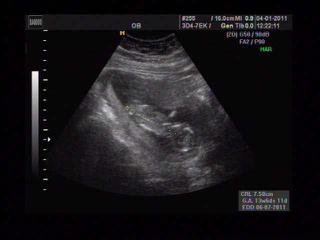

Kuratkol, krásný obrázek z ultrazvuku 😵 jak se cítíš?

Ahojky, tak jsme byli na kontrole - tentokrát i s manželem.